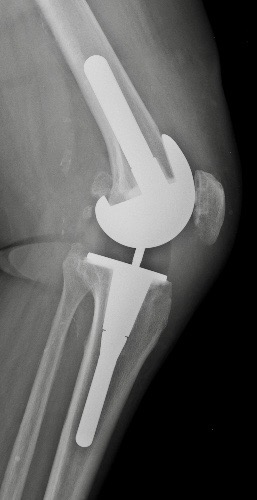

B. PTG à glissement avec quille d'extension tibiale

quille d’extension tibiale.

patients en surpoids ou ostéoporose